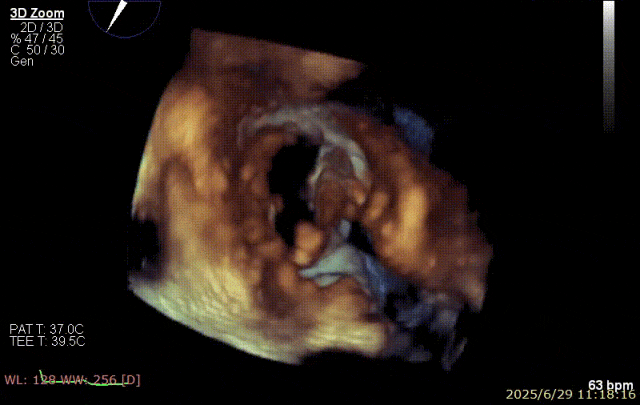

手术步骤

器械植入后二尖瓣 AP 径约 35 mm,CC 径约 39 mm;夹合器固定好、组织桥稳定,前瓣夹闭后瓣叶长度 25 mm,后瓣夹闭后瓣叶长度 7 mm;二尖瓣开放好,瓣口呈大小双孔,二尖瓣瓣口面积约 2.8 cm²,平均压差 1 mmHg,关闭可,二尖瓣反流明显减轻(从术前反流 4+显著改善至 1+),手术全程无需体外循环支持,无需输血,无需射线全超声引导。患者术后第二日回普通病房,患者恢复良好,术后第五日即出院。

2025 年 6 月 29 日,经过对术前超声和 CT 影像进行深入分析,团队制定了周密手术计划。在麻醉手术中心副护士长刘菊梅的充分术前准备和中国医学科学院阜外医院欧阳文斌教授的指导下,凭借团队的紧密协作和娴熟操作,单纯利用超声影像精确引导,通过导引导管系统经右胸、右房,穿房间隔,建立到达左房通路;经该通路将两枚二尖瓣钳夹成功植入二尖瓣病变部位进行夹持,夹合器位于 3 区及部分 2 区,固定好,运动协调,瓣叶启闭灵活,瓣口轻度反流,二尖瓣平均跨瓣压差 2 mmHg。手术圆满完成。